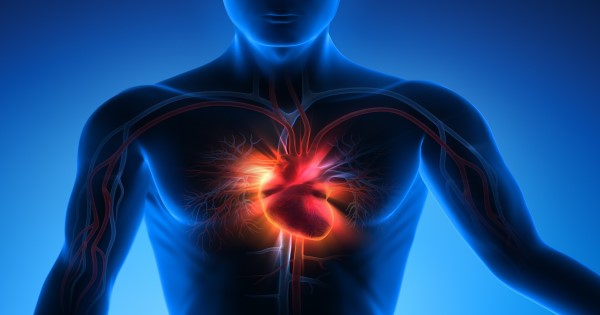

It can be said without any doubt that heart attacks are the most fatal health conditions in the world of medicine and that just makes this so much harder for people to watch.